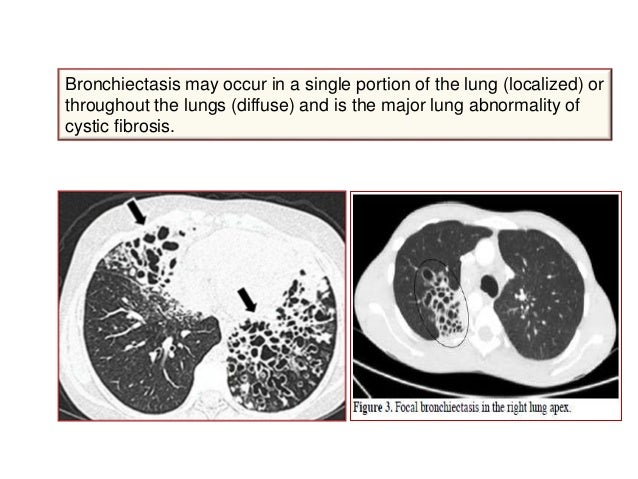

Cystic Fibrosis | Articles | Pediatrics In Review

plug lung mucous bronchus collapse bronchiectasis nejm causing citing articles